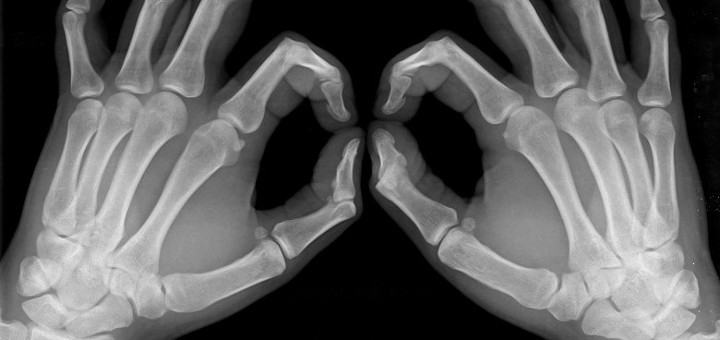

Az oszteoporózis, vagyis a csontritkulás azt jelenti, hogy a csontok törékennyé válnak. Ez a betegség legfőképpen az idősebb embereket érinti, nőknél a menopauza után alakul ki ez az állapot. A legutóbbi kutatások szerint a mértéktelen cukorfogyasztás okozhat csontritkulást, de felelőssé tehető a szív- és érrendszeri betegségek, a cukorbetegség és más krónikus állapotok kialakulásáért is.

A cukorbetegség, a csontritkulás és magas vérnyomás összefüggései…